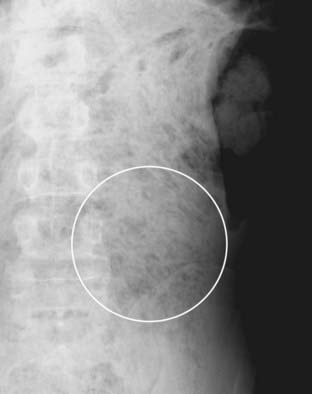

Figure 13-4 Appearance of stool.

Stool is recognizable by the multiple, small bubbles of gas present within a semisolid-appearing soft tissue density (white circle). Stool marks the location of the large bowel and can help in identification of individual loops of bowel on conventional radiographs. This patient has a markedly dilated sigmoid colon from chronic constipation.